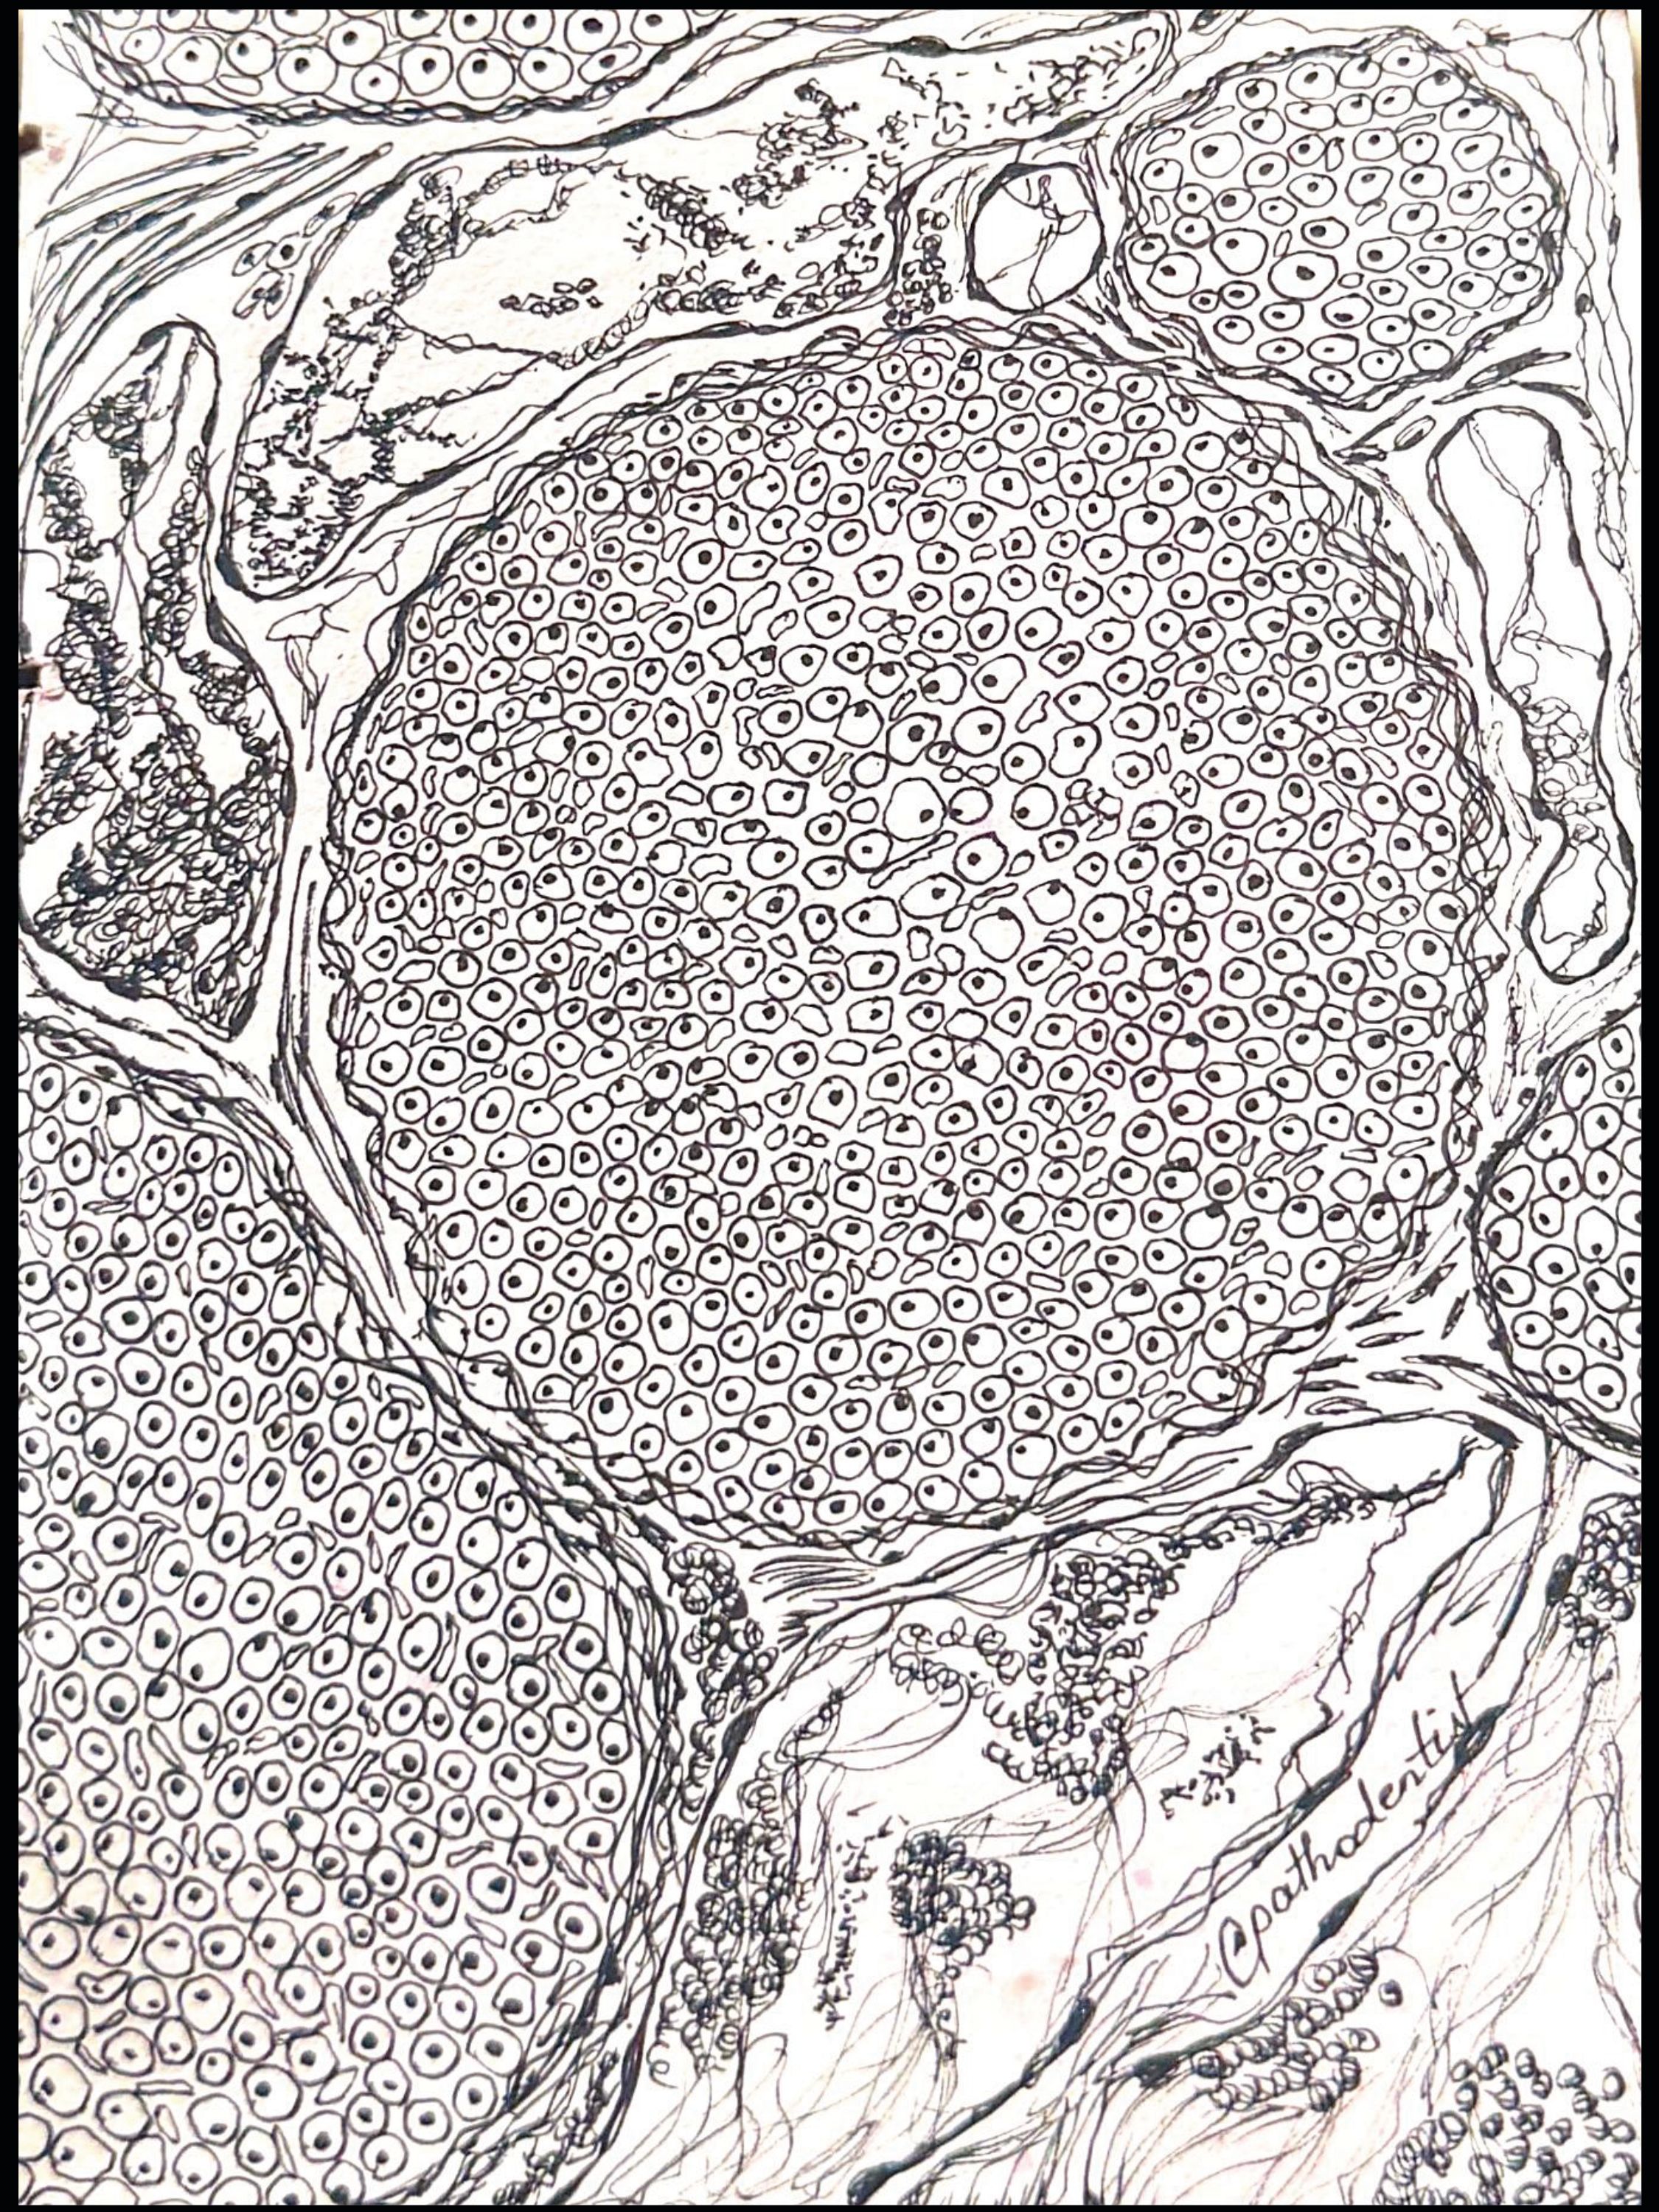

Peripheral nerve by Pranjali Mandurkar, Oral and Maxillofacial Pathologist, Goa Dental College and Hospital, India. A monochromatic sketch of a cross-section of peripheral nerve using micro pigment ink.